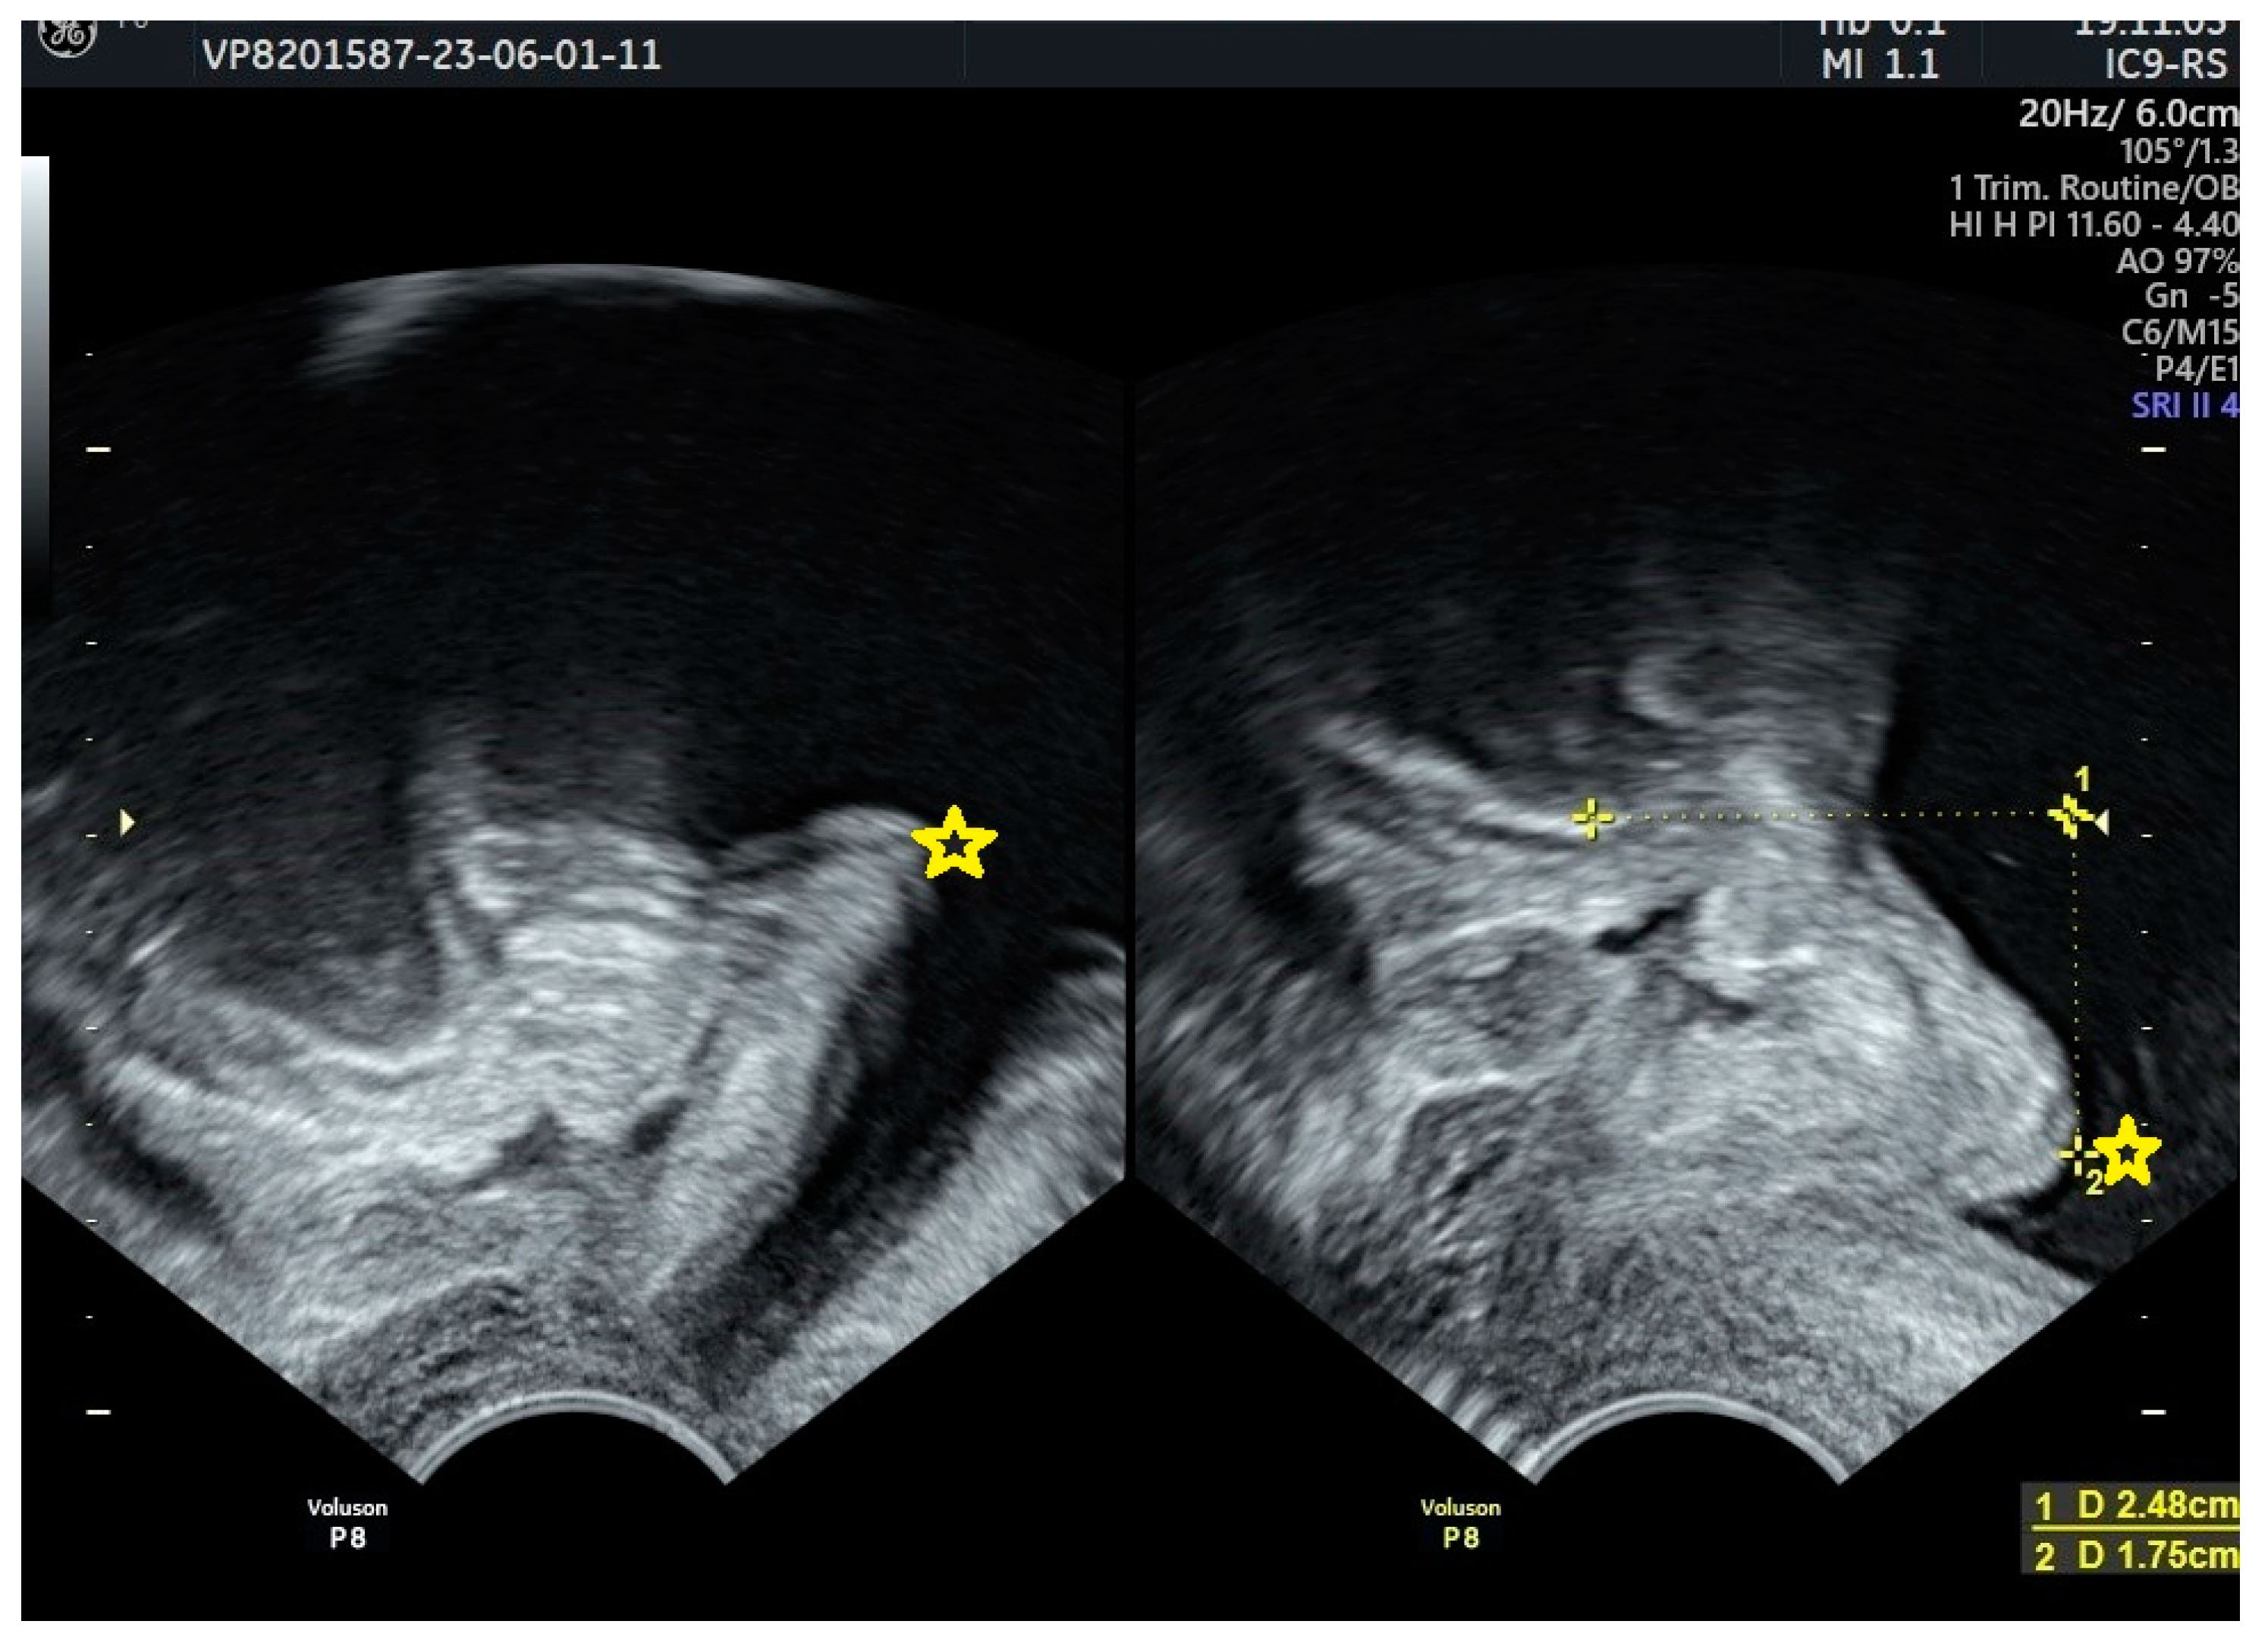

| Taithongchai et al., 2021 [71] | Higher risk in patients with Group III sling shape. | |

| Chene et al., 2008 [51] | Tighter sling angulation in the affected patients. | |